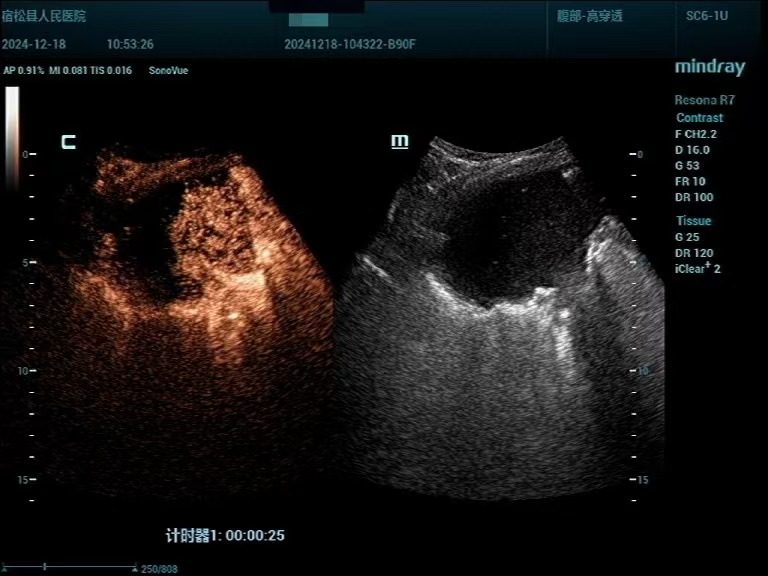

患者男性,83岁,发现肺部占位入院。其胸部CT提示右肺上叶肿块,纤支镜未能取到病理结果、建议进一步检查,呼吸内科评估后考虑肿块为恶性肿瘤的可能性大,需要进一步行活检以明确病理诊断。在征求家属意见后,超声诊断中心为其进行超声造影联合超声定位下肺肿块穿刺活检,该患者肺部病灶位于右肺上叶,结合不同频率超声探头检查,清晰显示了病灶内部结构及血流灌注情况。造影结束后,初步判断该肿物为恶性肿瘤的造影模式,在超声引导下,避开病灶大血管及坏死区,穿刺针取出肺部病变适量标本,活检病理结果提示鳞状细胞癌,为该患者的下一步诊治提供了充分依据。

▲超声造影:右肺上叶团块超声造影符合肺Ca伴坏死表现